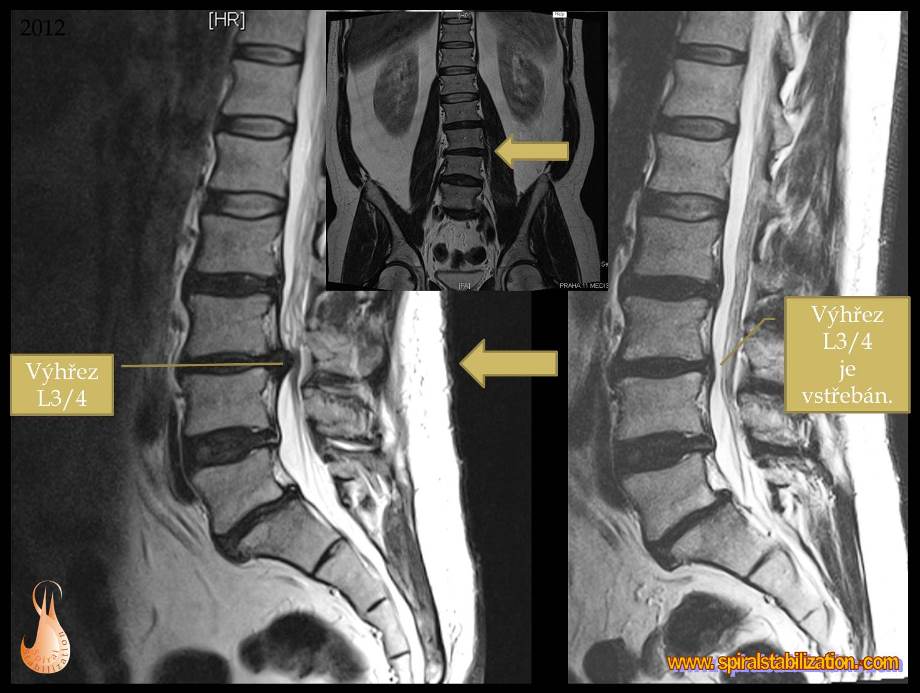

Výsledky hernia L3/L4